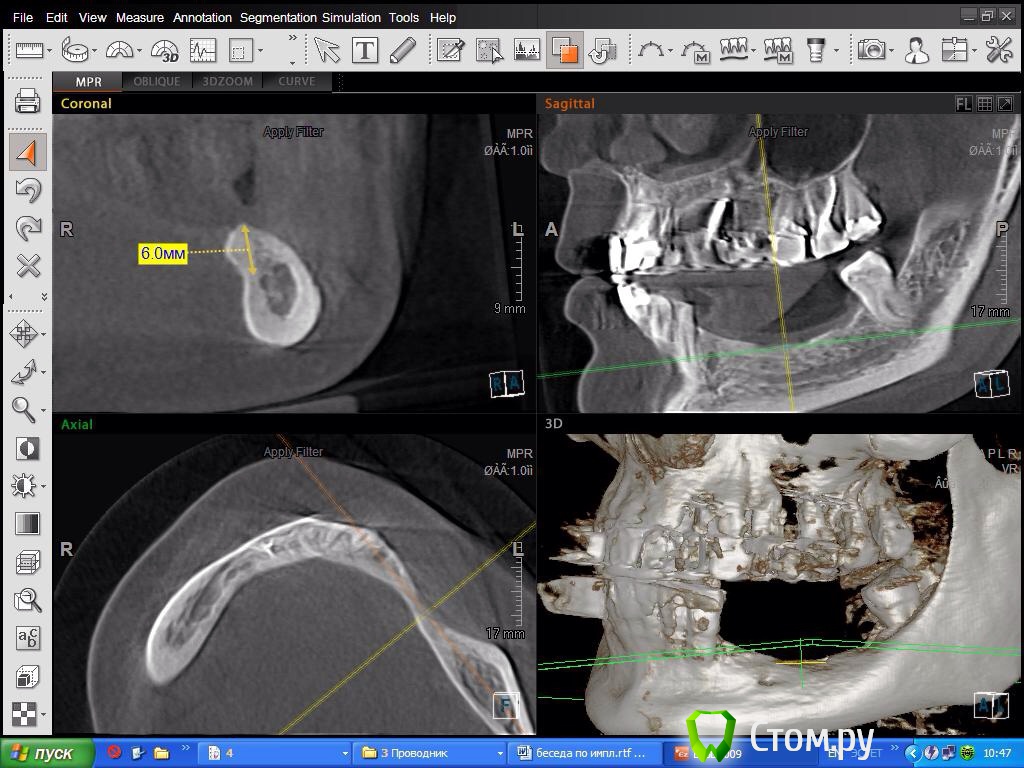

DoktorDre Опубликовано 8 октября, 2014 Автор Поделиться Опубликовано 8 октября, 2014 (изменено) Спасибо!Это все замечательно! Как обойти торчащие вверх металисы?? Не прикручу же на них ламинат!Особенно меня смущает 45-не расщепить, и металис совсем близко Изменено 8 октября, 2014 пользователем DoktorDre Ссылка на комментарий

DoktorDre Опубликовано 8 октября, 2014 Автор Поделиться Опубликовано 8 октября, 2014 Почему не расщепить? ,,,1) Будет сдавлен менталис в обл 45 2) много коркиткалки- плохо щепится 3) дефицит по вертикали только усугубится после расщепления 1 мм как правило уходит.. Ссылка на комментарий

DoktorDre Опубликовано 9 октября, 2014 Автор Поделиться Опубликовано 9 октября, 2014 Мане,Дмитрий, почему не ламинаты? Я уже собрался оставить область 44 в покое, обл 45,46 отвертикалить, и 46 45 импланты+ консоль. Крышу гаража не могу сделать- жадное руководство не хочет слушать про уз. Ссылка на комментарий